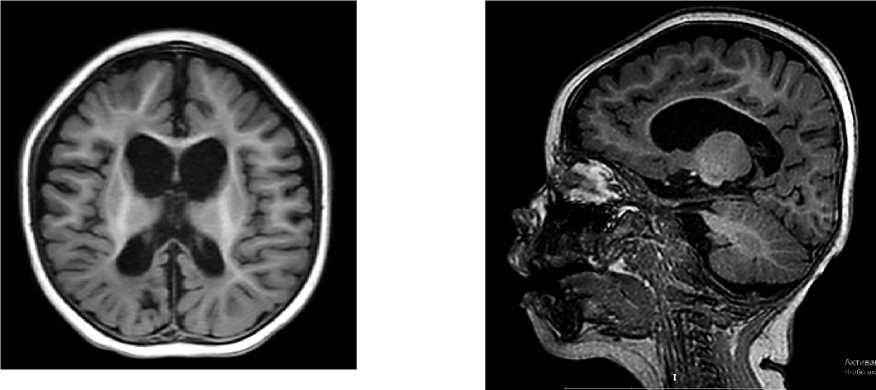

Магнитно-резонансная томография. МРТ головного мозга (T1-взвешенные изображения в сагиттальной и аксиальной проекциях) выявила выраженную диффузную атрофию обоих полушарий со вторичной микроцефалией, расширение ликворных пространств и вентрикуломегалию экс-вакуо. В перивентрикулярных отделах белого вещества определялись изменения, характерные для перивентрикулярной лейкомаляции, что соответствовало тяжелому гипоксически-ишемическому поражению головного мозга перинатального периода (Рисунок 2).

Рисунок 2. МРТ головного мозга